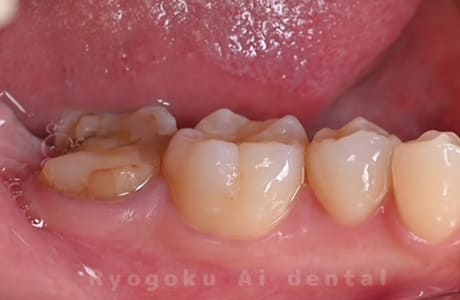

Case20

-

- 原因

- 重度カリエス

- 治療内容

- クラウンレングスニング

- 治療費用

- 44,000円

他院で抜歯と宣告され、当医院を受診された患者様です。クラウンレングスニングを行い、保存を行いました。経過良好です。

<リスク・副作用>

手術後は痛み、腫れ、痺れ、青あざなどの副作用が生じます。痛みは痛み止めを処方しますが、腫れ、青あざは1週間程度生じる場合があります。また、部位によっては神経の走行が複雑で、痺れが残り、長期的にお薬を処方する場合があります。